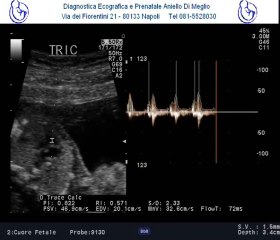

Difetto del setto atriale tipo ostium primum